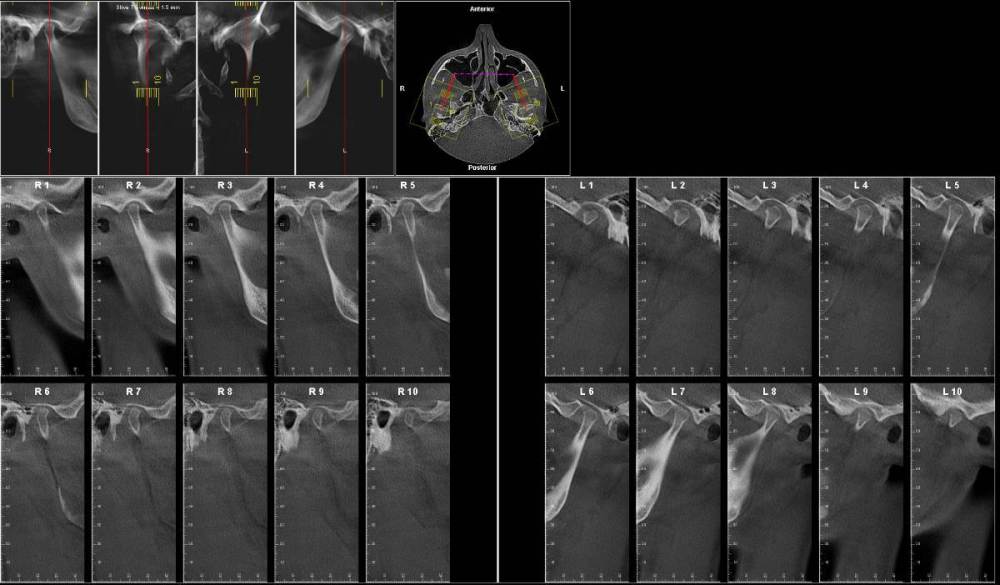

Lotos123 Опубликовано 24 ноября, 2022 Поделиться Опубликовано 24 ноября, 2022 чувствую боль справа и щелчки слева Ссылка на комментарий